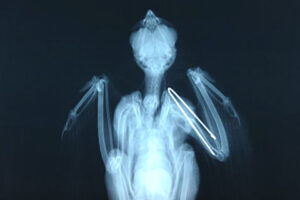

翼をしっかりと固定

鳥の骨は竹筒のように中空になっており、中にピンを入れただけでは折れた骨が安定しません。このため、特殊な髄内ピンとギプスを一体化させ、翼をしっかりと固定しました。ようやく翼が正し位置に戻り、身体への負担がだいぶ軽くなったようです。

手術から約3週間。レントゲンで骨がしっかり付いたことを確認し、ギプスと骨のピンを取り除きました。複数の止まり木を計画的に配置した入院室の中で、枝移りをしながらのリハビリを開始。翼もきれいなV字型に開くようになってきました。